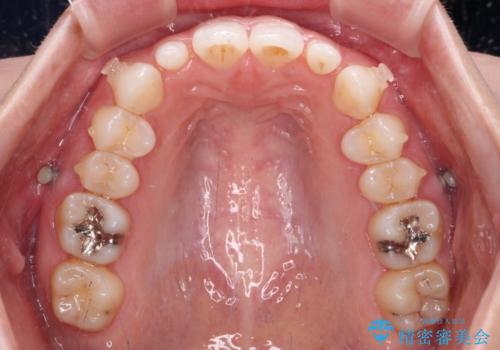

- 前歯のデコボコと左右の矮小歯を気にして来院された患者様です。

矮小歯の前後にスペースを作るようにインビザライン矯正治療を計画し、矯正治療後にオールセラミッククラウンによる補綴治療を行うこととしました。

アンカースクリューを用いて上顎歯列全体を後方移動させ、極力過蓋咬合も改善されるよう計画しました。